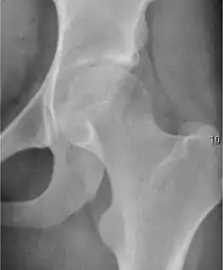

Projectional radiography ("X-ray") is the first imaging technique of choice in hip pain, not only in older people with suspected osteoarthritis but also in young people without any such suspicion. In this case plain radiography allows categorization as normal hip or dysplastic hip, or with impingement signs, pincer, cam, or a combination of both.[1]

X-Ray

Projectional radiography ("X-ray") is currently useful not only in older people in whom osteoarthritis of the hip is suspected but also in younger people without osteoarthritis, who are being evaluated for femoroacetabular impingement (FAI) or hip dysplasia.[1]

Plain radiography allows us to categorize the hip as normal or dysplastic or with impingement signs (pincer, cam, or a combination of both). Besides these, pathologic processes like osteoarthritis, inflammatory diseases, infection, or tumors can also be identified (Figure 1).[1]

Figure 1.

Radiography in normal hip

X-ray in pincer impingement type of hip dysplasia

X-ray of cam

Hip in osteoarthritis

Septic arthritis